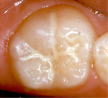

これは、萌出間もない六歳臼歯の咬合面の溝にフッ化物含有のセメントなどで一時的に塞ぎ、う蝕予防のために行う方法で、はっきりとターゲットを絞った永久歯のう蝕予防法である。

なお、シーラントは破折したり、外れやすいので定期的に管理の必要性があり、シーラントが取れたままだと逆にう蝕になりやすくなるので注意が必要である。

シーラント前 シーラントをした状態